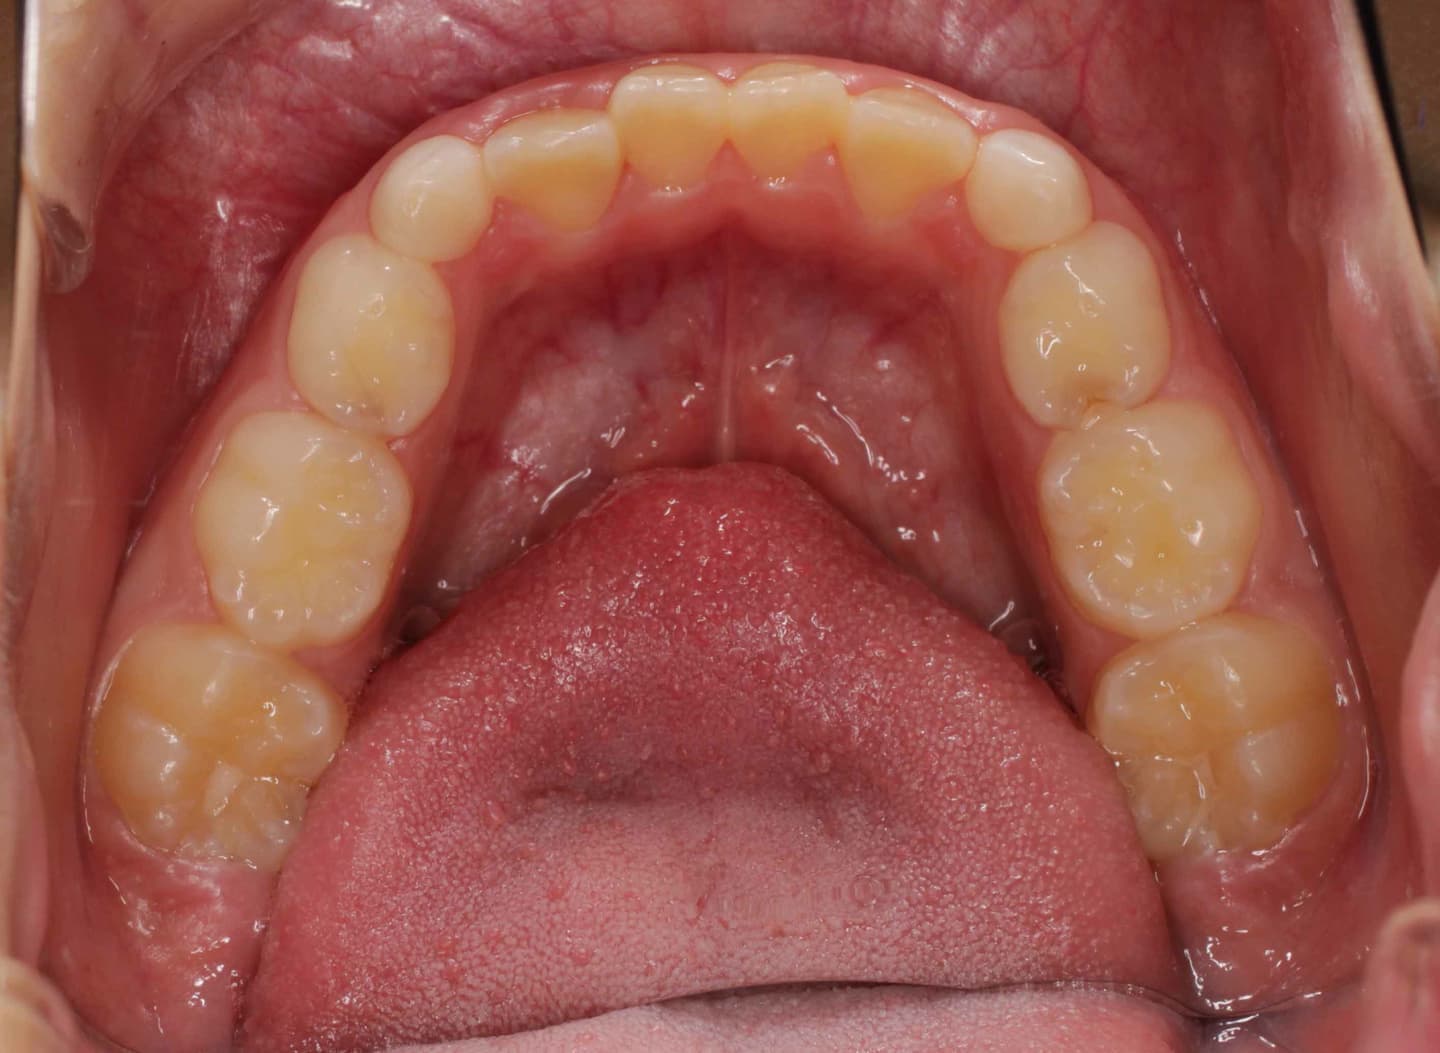

治療後(12ヶ月後)